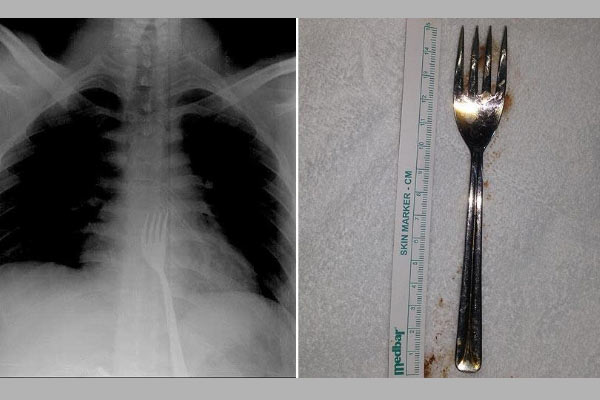

Konyalı genç 15 santimetrelik çatal yuttu

Konya'da bir genç, 15 santimetrelik metal çatal yuttu. Yemek borusuna kadar inip midede kalan çatal, ameliyatla çıkarıldı.

Çeşitli sağlık problemleri olan 20 yaşındaki O.A'nın çatal yuttuğunu fark eden ailesi, oğullarını Necmettin Erbakan Üniversitesi Meram Tıp Fakültesi Hastanesine götürdü. Çekilen röntgen filmlerinde, çatalın midede olduğu görüldü. O.A'nın midesinden 15 santimetrelik metal çatal, başarılı operasyonla çıkarıldı. O.A, taburcu edildi.

YEMEK BORUSUNA KADAR İNİP MİDEDE KALDI

Kontrollerde çatalın yemek borusunun sonuna kadar inip midede kaldığını gördüklerini aktaran Erikoğlu, büyük olması nedeniyle çatalı operasyonla mideden küçük kesiyle çıkardıklarını ifade etti. Küçük bazı yabancı cisimlerin mideden atılabildiğini anlatan Erikoğlu, "Yabancı cisim düz yutulmuş olsaydı, ciddi sıkıntılar doğabilirdi. Çatal tersten yutulduğu için vücuda bir zararı olmamış. Bugüne kadar çatal yutulmasıyla ilk kez karşılaştık." diye konuştu. Erikoğlu, yabancı cisimlerin vücuda vereceği zararın büyük olabileceğini söyleyerek, ailelerin özellikle bu konularda dikkat etmesi gerektiği uyarısında bulundu.